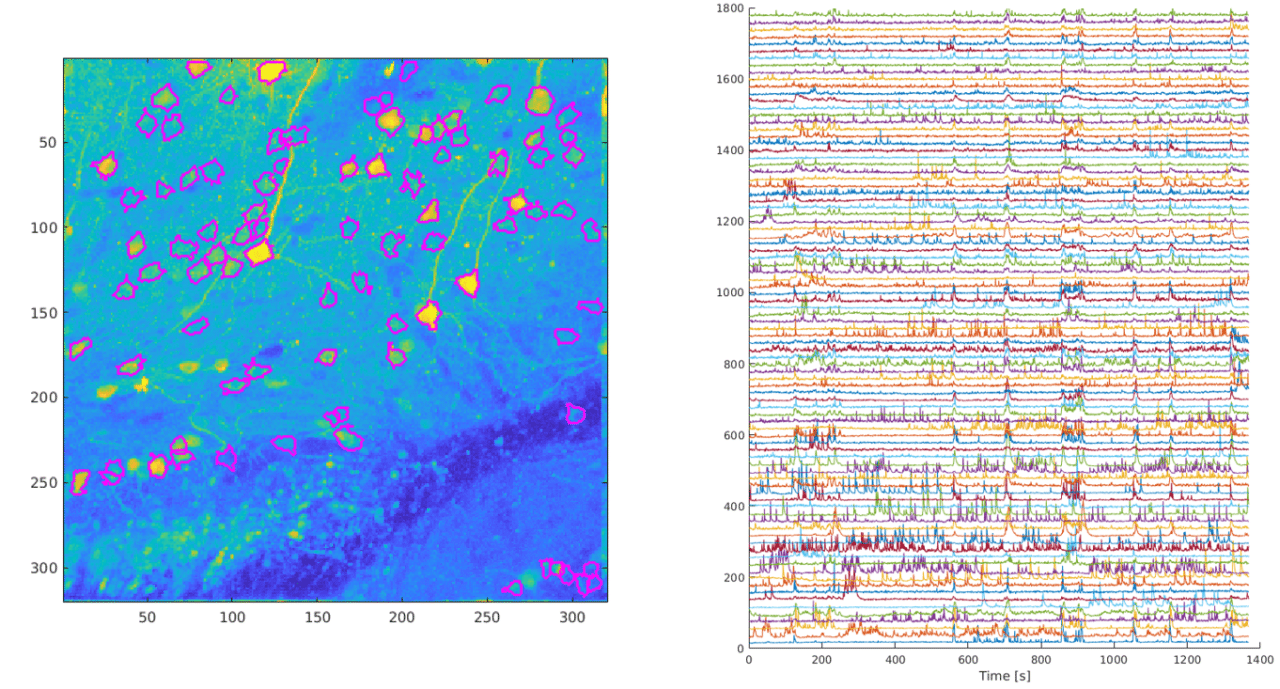

Cortex-wide calcium signaling (dF/F) in a living, behaving mouse expressing GCaMP in excitatory neurons. Image obtained at Neurotar using wide-field calcium imaging on the Invigilo setup.

The activity of individual neurons can be tracked over extended periods of time when calcium signaling is imaged using two-photon microscopy. Data obtained at Neurotar.

In a typical two-photon calcium signaling assay, we image neuronal activity over time in a certain brain region. Due to low phototoxicity and the ability to obtain high-resolution images, our two-photon microscopy calcium imaging assay enables us to track the activity of individual neurons over extended periods of time. This provides a wealth of data, as illustrated above, which increases statistical power. In addition, we can re-examine the same field of view at different time points over several months. This enables us to measure neuronal activity in the same neurons before and after, for example, a perturbation (illustrated below for spinal cord injury) or drug treatment. Measuring control and treatment conditions on the same neurons decreases variability and reduces the number of animals needed for each study.